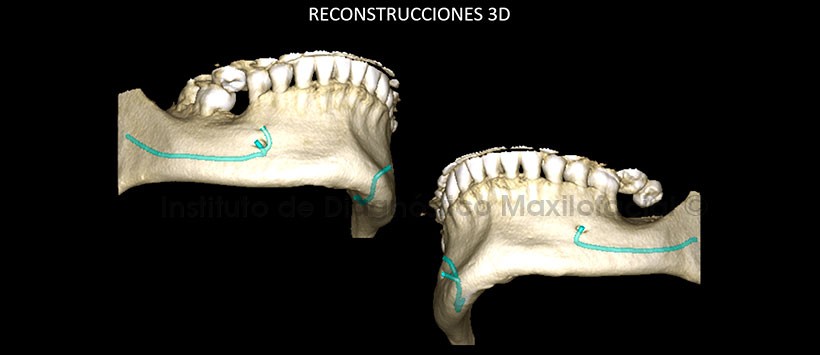

El software Romexis nos brinda diferentes opciones de reconstrucción 3D, como por ejemplo la opción radiográfico matizado; que es de mucha ayuda para la evaluación de esta variante anatómica (Fig. 4).